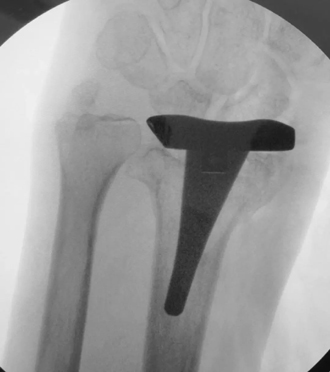

假体置入后术中透视图

历经3个多小时的手术,患者的桡骨远端被全新的人工假体所代替。同时因采用机器人辅助精准定位,假体摆放位置非常满意,完全实现术前模拟情况。相信经过一段时间的康复锻炼,患者一定能够获得满意结果。